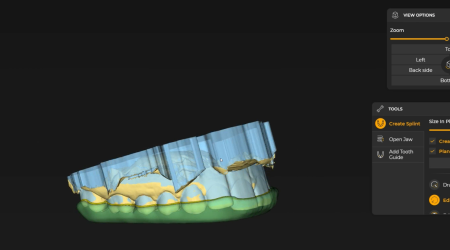

Digital Smile Design (DSD)

Seeing the Outcome Before It Exists

Digital Smile Design is not about cosmetic promises.

It is about alignment — between facial structure, bite function, and natural expression.

Before any irreversible step:

- Your facial proportions are analyzed

- Tooth shape, length, and symmetry are evaluated digitally

- The smile is designed in harmony with how you speak and rest

This allows patients to:

- Understand the direction of treatment visually

- Adjust expectations early

- Move forward without uncertainty

For many patients, this step alone removes the fear of regret.

With Digital Smile Design, patients can visualize the planned outcome before treatment starts. This allows adjustments to be made early — when changes are simple and reversible — instead of later, when they are not.

This process significantly reduces second‑guessing after treatment.